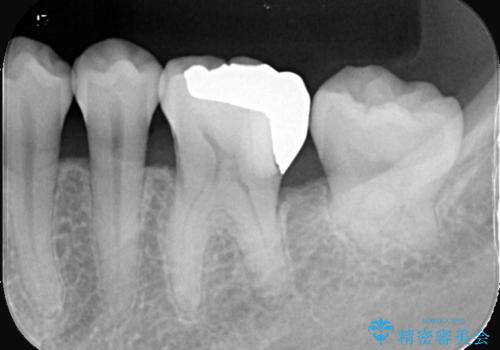

- 銀歯の下に虫歯が見つかりました。一度治療されている歯であり、レントゲン上では虫歯が神経に近い位置まで進行している様子が確認されました。

ただし、自発痛の既往はなく、歯髄診の結果も正常であったため、虫歯除去中に露髄した場合には生活歯髄療法(VPT)を行う方針としました。